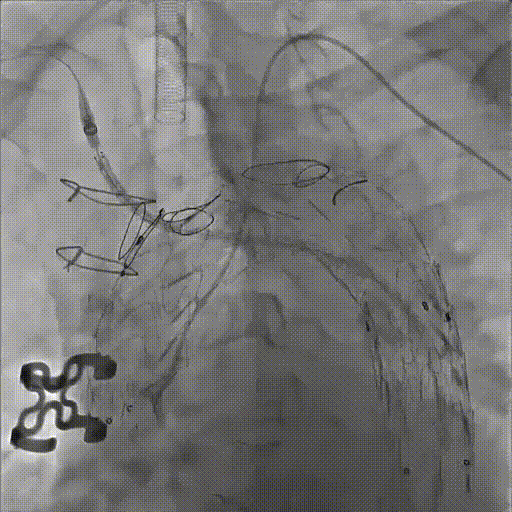

★ Case 5

男性,79岁,胸痛10+天

既往史:既往诊断高血压,未规律服药及监测血压

个人史:吸烟40余年,日均20支

头颈部CTA提示:颅内大脑后动脉P2段重度狭窄

夹层动脉瘤CTA:升主动脉局限性夹层、主动脉壁内血肿合并穿透性溃疡

主动脉造影后,降主动脉限制支架置入,导入近端主体支架

升主动脉后造影定位后,释放近端主体支架,术毕造影